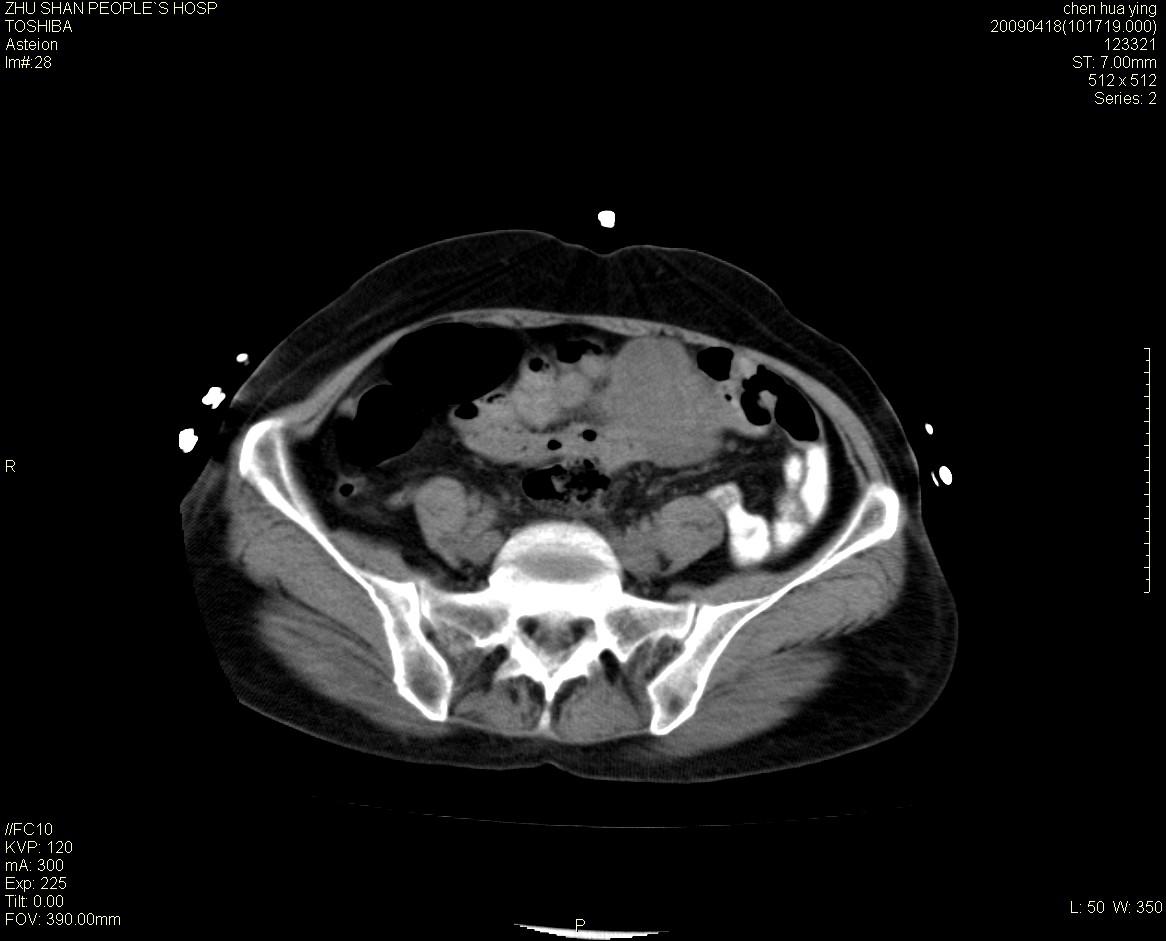

女性病人 65岁 腹部包块半年余结肠造影未见异常.

病灶略呈圆形有分叶状,上部层面呈实性,右侧见圆形低密度区,灶内见团块状钙化,病灶下方与肠管分境不清,考虑间质瘤可能性大,建议肠道准备后增强